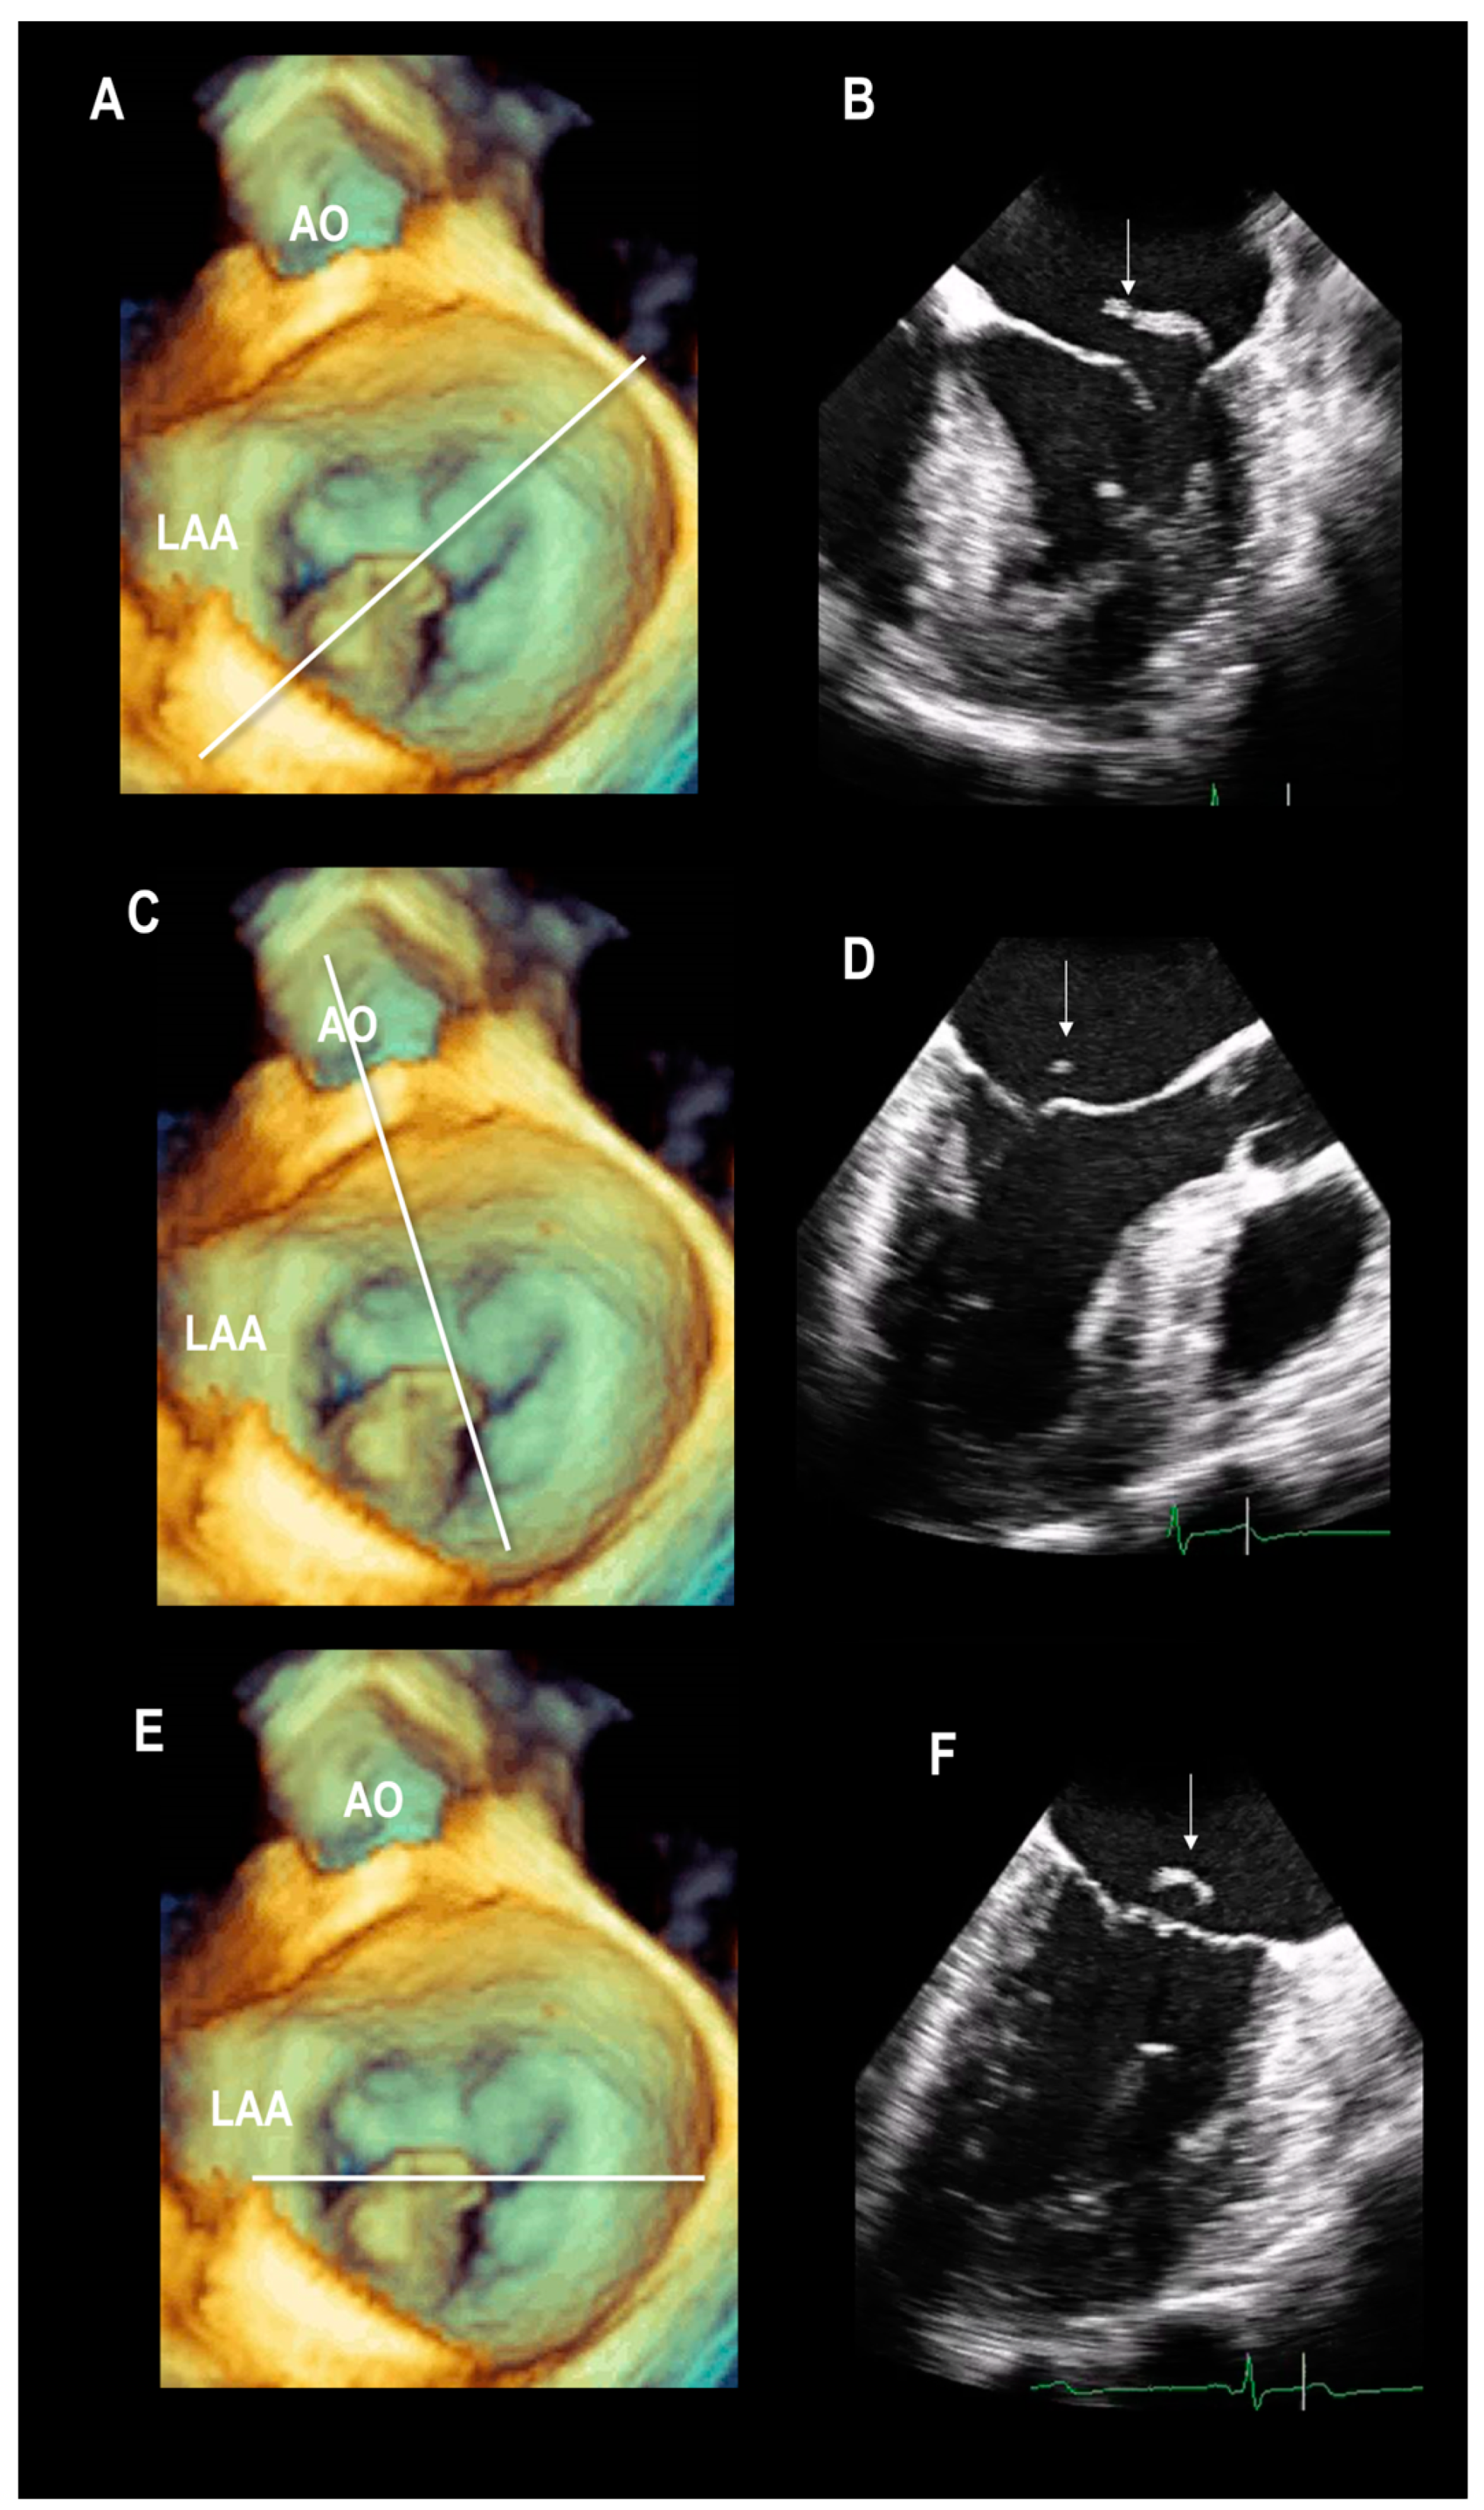

2.1. Scenario # 1

Multiple Perspectives